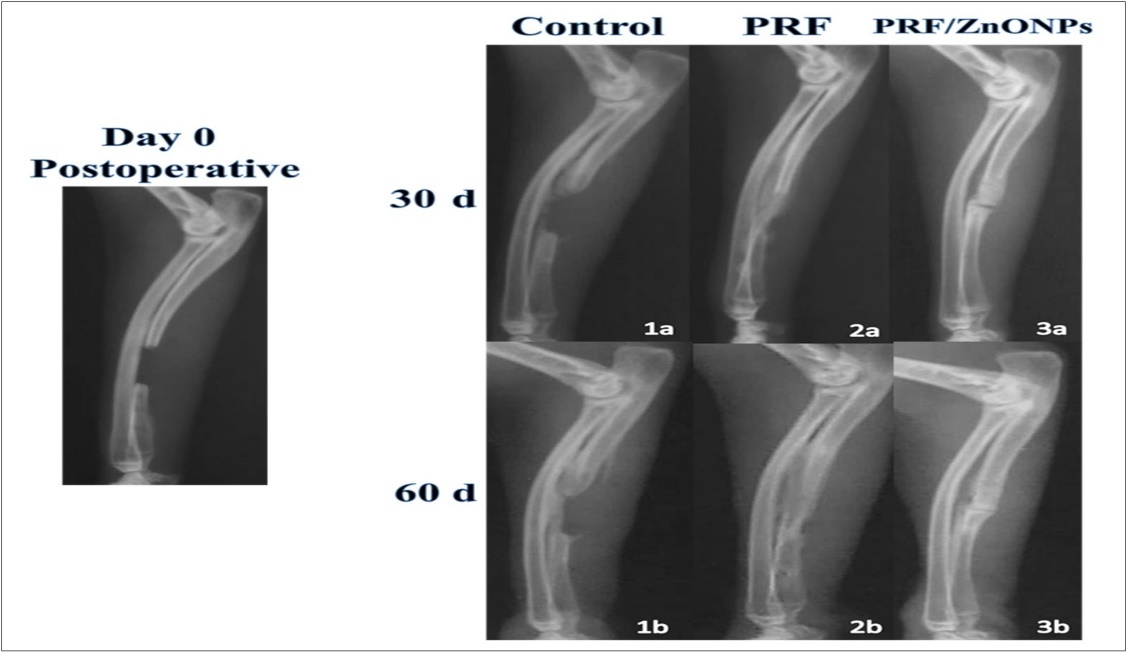

Compared to the immediate postoperative radiographs, healing of the defect was determined by evaluating the radiographs in each group at the 1st and the 2nd postoperative months for bridging the gap, and the healing capacity of each treatment. The healing score was measured by different independent operators using a ruler to measure the percentage of newly formed tissue in the defect depending on the apparent greyscale. Our healing score was designed as follows, score 1 = less than 25% healing, score 2 = 25-50% healing, score 3 = 50-75% healing, and score 4=75-100% healing. Bridging of the gap is considered present if any newly formed growth was found to connect between the two extremities of the defect on X-ray films. Otherwise, gap bridging is considered absent. The higher healing score with gap bridging was considered to have more new bone formation.

During the current study, no serious complications and death were observed and the healing took place in all surgical wounds by the first intention. Clinical wellness was observed in all rabbits as early as the second postoperative day. Compared to the postoperative radiographs, the addition of PRF and ZnONPs to segmental ulnar CSD of 12-mm length resulted in obvious radiographic changes (Table 1, Figure 2), and the statistical analysis showed a significant difference in the healing score between the three experimental groups (P = 0.000) at all-time points (P = 0.000- 0.003) during the study.

Figure 2.Showing lateral radiographs of the three experimental groups (Control, PRF and PRF/ZnONPs) at 0, 30 and 60 postoperative days.

Concerning bone healing in the region of interest, treatment of CSD by adding PRF either alone (PRF group) or in combination with ZnONPs (PRF/ZnONPs group) resulted in a highly significant (P = 0.000) increase in the healing score of CSD versus the Control group. On the 30th postoperative day, the healing score was 3.0 (2.0- 3.0) and 4.0 (4.0- 4.0) in PRF and PRF/ZnONPs groups respectively versus 2.0 (1.0- 2.0) in the Control group. On the 60th postoperative day, complete filling of the CSD represented by 0.4 healing scores was observed in both treatment groups, versus 2.0 healing score and incomplete filling in the Control group.

In terms of bridging callus, there was a significant difference between times within a group (P = 0.000- 0.001) but a non-significant difference between groups within time. On the 30th day, 62.5% of rabbits in both treatment groups showed gap bridging versus no bridging in the control group with a significant difference (P = 0.018) between groups within this time point. At the end of the study, 75% of the control group rabbits started to show some sort of bridging callus meanwhile all rabbits of both PRF and PRF/ZnONPs groups exhibited complete bridging of the gap.

Comparing the radiographic density of the healed bone, both treatment groups exhibited higher bone density compared to the Control group. In all rabbits of the combination group, maximal density was early obtained on the 30th postoperative day.